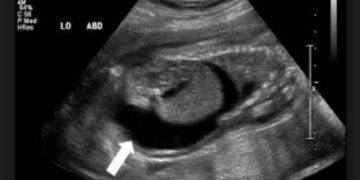

Etiket: Yavru Zarları Hidropsu Nedir